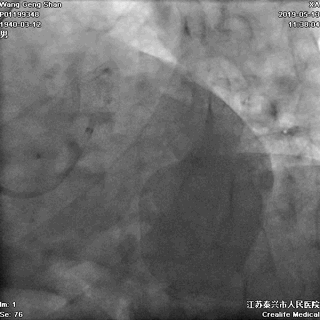

右头位定位

蜘蛛位定位